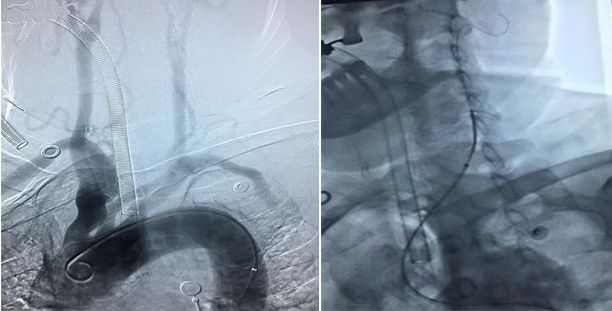

19:00:急血管内治疗术,行股动脉穿刺。

通路不畅,股动脉迂曲用加硬导丝支撑

III型弓,应用望眼镜同轴技术,导管到位

造影示:颈内动脉闭塞,眼动脉有代偿,血管闭塞原因决定血管再通方式!

找到闭塞血管部位,狭窄?夹层?

造影右侧椎动脉闭塞,右侧颈总动脉

左侧颈总、左侧椎动脉

左锥造影V4段先天性病变(狭窄?)

右椎入路微导管手推造影,寻找血管闭塞位置